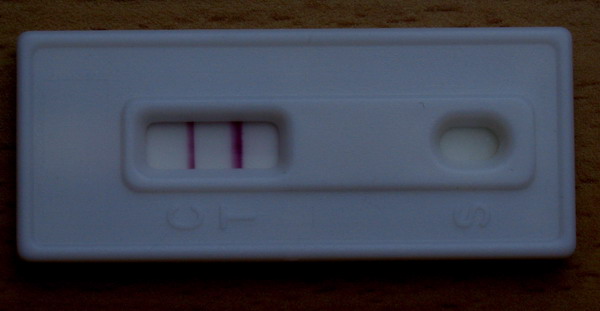

én csalok, és olvaslak a missed ab-ben is.

De ezt a csodás fotót szívesen nézegetem több helyen is!

kép

kép kép 2

kép 2